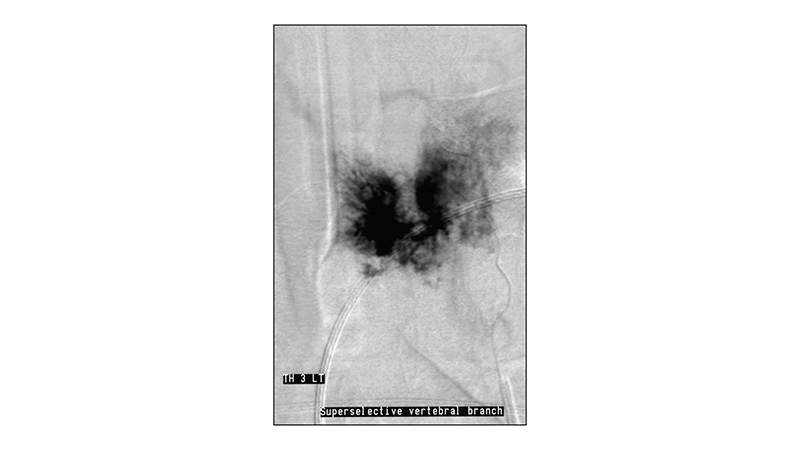

Εικόνα 1: Αξονική τομογραφία, λεπτές τομές στο επίπεδο του Θ3 σπονδύλου: Εικόνα οστικής αραίωσης με έντονες δοκιδώσεις του σώματος του Θ3, εικόνα χαρακτηριστική αιμαγγειώματος σπονδύλου. Το οστικό όριο του σπονδύλου διατηρείται.